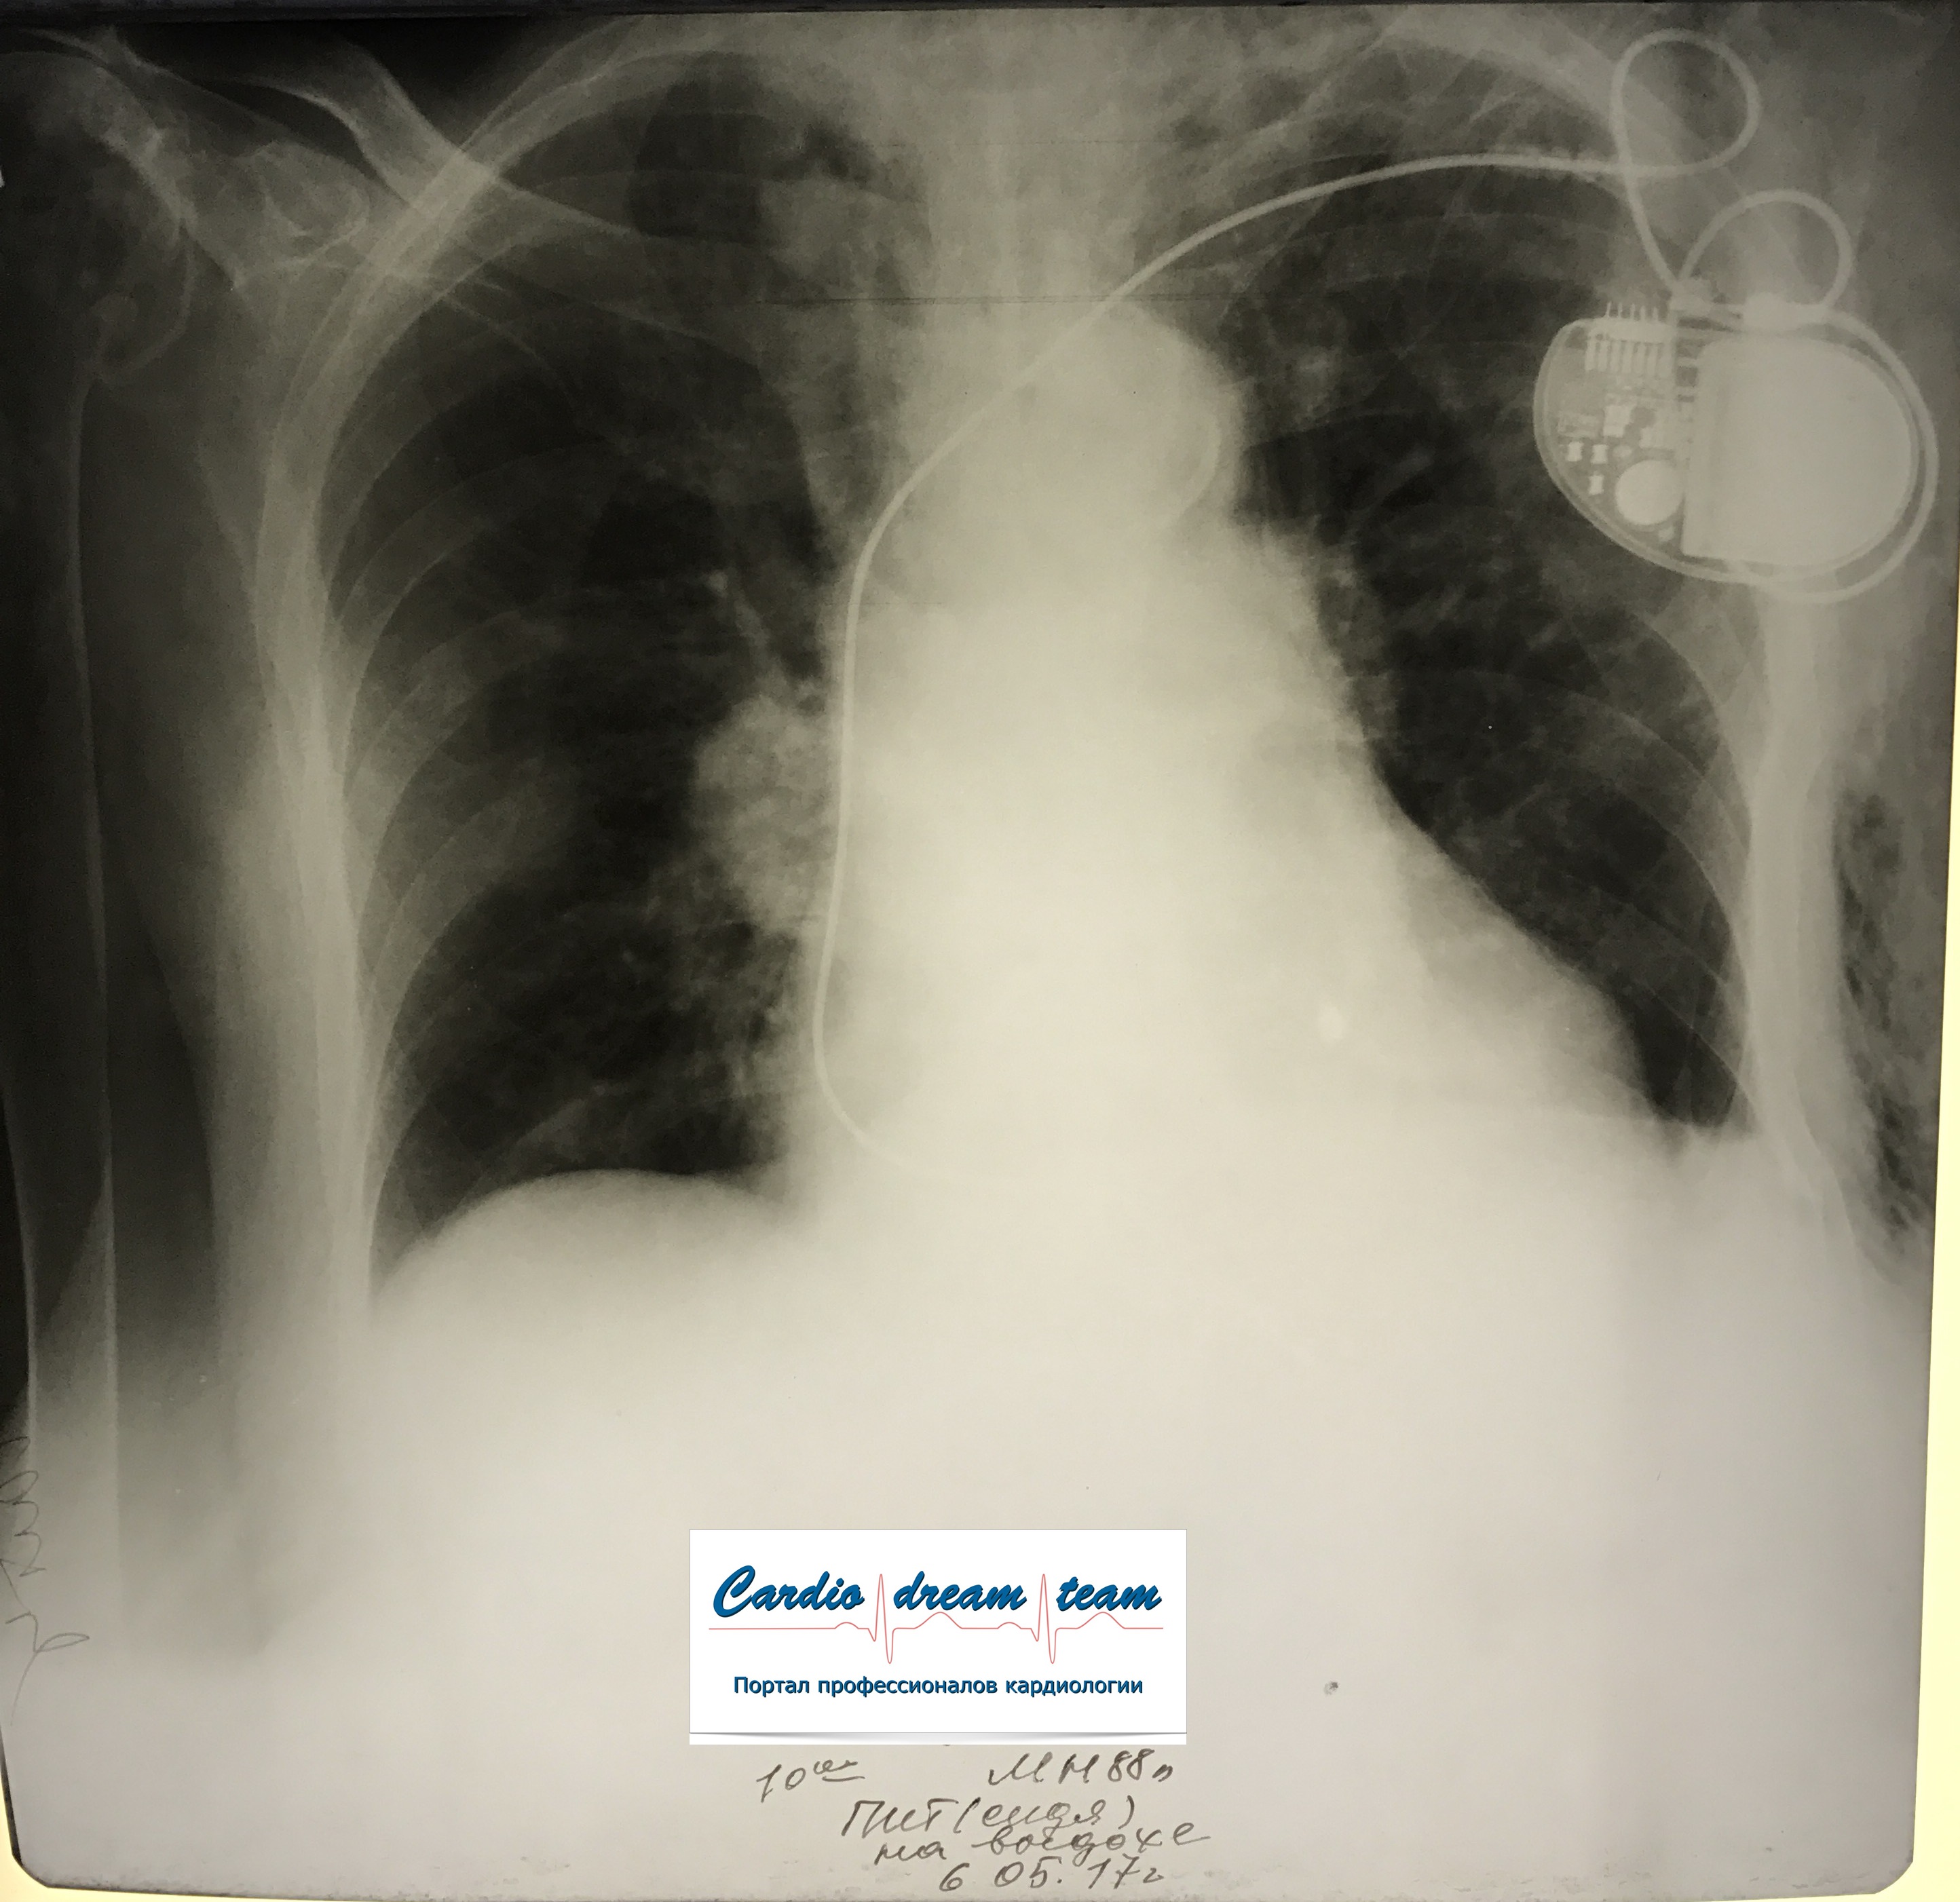

Проведена рентгенография органов грудной клетки в прямой проекции, положение полусидя, условия ПИТ, Р-контроль Легочные поля: Отрицательная динамика: правое легкое поджато к корню. Тень средостения резко смещена влево. Выраженная подкожная эмфизема мягких тканей грудной клетки справа. Тень подключичного катетера в проекции ВПВ. Легочный рисунок: диффузно деформирован за счет пневмосклероза, сгущен справа Корни: тень средостения смещена влево Синусы: нечеткие Сердце: широко лежит на диафрагме (позиционно) ЗАКЛЮЧЕНИЕ: Правосторонний пневмоторакс, отрицательная Р-динамика. Эмфизема мягких тканей грудной клетки. Пневмосклероз. Р-контроль.